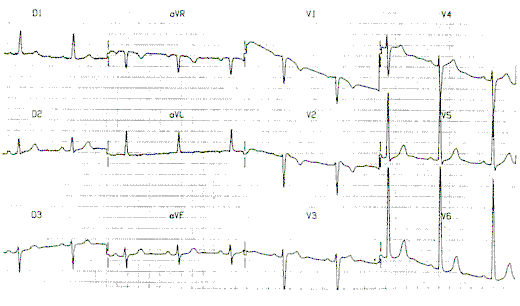

L’infarto

La necrosi di una porzione del tessuto miocardico comporta variazioni della corrente di depolarizzazione e ripolarizzazione, che si manifestano all’elettrocardiogramma con una serie di successive alterazioni

Il sopraslivellamento del tratto ST è l’alterazione elettrocardiografica che permette di identificare un infarto acuto.

La presenza di un’onda Q anomala è l’alterazione elettrocardiografica che permette di identificare un infarto avvenuto in precedenza. Essa rappresenta una sorta di cicatrice elettrocardiografica.

Le alterazioni elettrocardiografiche determinate dall’infarto risultano localizzate alle derivazioni che esplorano le zone interessate dalla necrosi.

L’elettrocardiogramma permette per tale motivo di identificare quale zona del cuore è stata interessata da un infarto.

In caso di infarto anteriore le alterazioni elettrocardiografiche interesseranno le derivazioni precordiali

In caso di infarto inferiore le alterazioni elettrocardiografiche interesseranno prevalentemente D2, aVF e D3